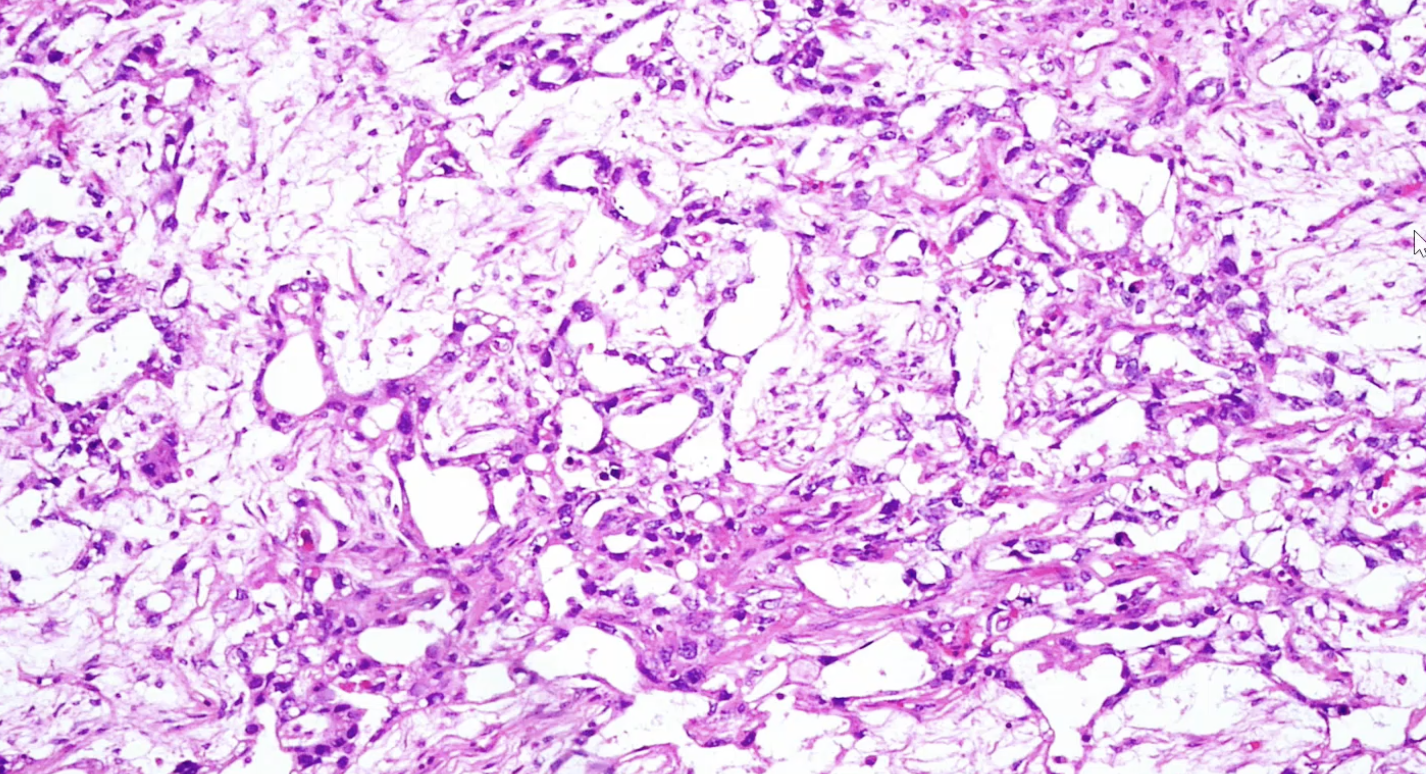

Yolk Sac - 16 to 17 mo old. Elevated serum AFP 20% of children may have metastasis

Microcystic Yolk Sac Tumor

Schiller-Duval Body Yolk Sac

Hyaline globules of yolk sac tumor

Yolk sac tumor